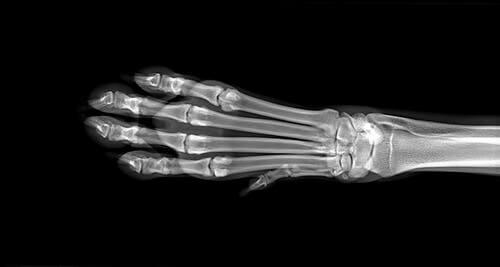

Pour déterminer la cause de l’inflammation, le vétérinaire réalisera une série de tests. Y compris des analyses de sang et d’urines, ainsi que des radiographies des membres de l’animal. Dans le cas où ces dernières ne sont pas concluantes, une IRM peut être nécessaire. Si l’on suspecte un ostéosarcome, une biopsie osseuse sera effectuée.